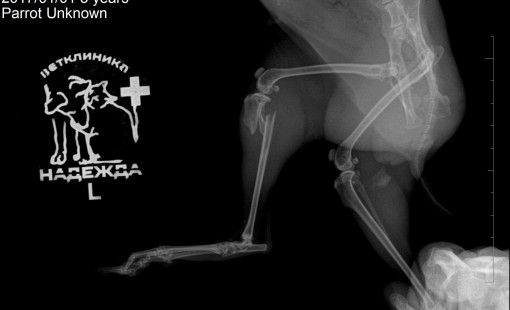

Случаи из практики

Ветеринарная клиника Надежда

За более чем 30-ти летнюю практику наши ветеринары сталкивались в различными случаями болезней и травм животных. Это дало нам огромный опыт в лечении и реабилитации. Мы беремся даже за самые сложные случаи! С любовью и заботой относимся к животным, стараемся сделать так, чтобы они испытывали минимум дискомфорта во время лечения и реабилитации.